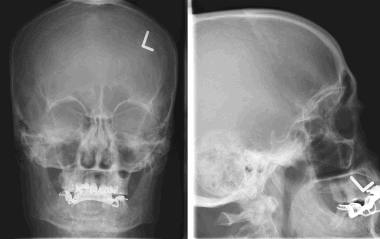

8. На рентгеновском снимке во фронтальной плоскости хорошо заметно кальцифицированное образование в области лобной пазухи. На снимке в латеральной проекции образование визуализируется кверху от решетчатой пластинки. Несмотря на то, что по результатам исследования можно заподозрить, обнаруженные признаки неспецифичны, и поэтому обнаруженное внутричерепное образование требует дообследования при помощи КТ.

Большинство рентгеновских снимков не отображают признаков наличия заболевания. Менингиомы типа en plaque характеризуются диффузным гиперостозом, чаще в области крыла клиновидной кости и птериона. Такие результаты исследования с большой долей вероятности свидетельствуют о наличии

болезни.